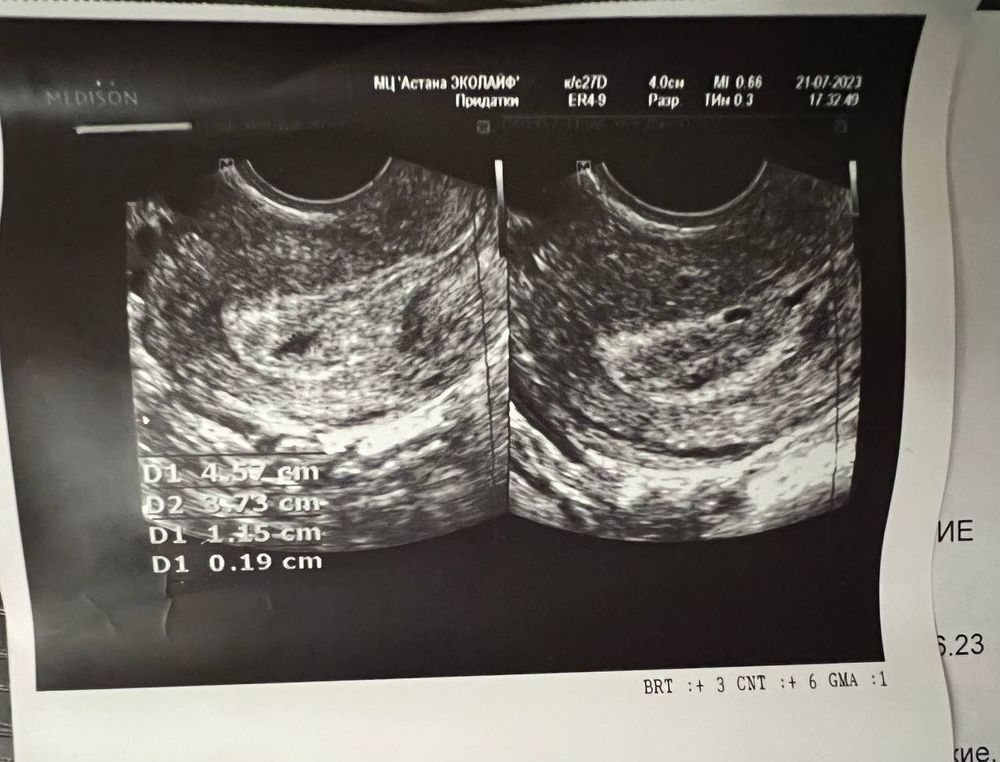

жидкостные следы и анэхогенные включения в эндометрии

Настя , представляете, сегодня была на узи и мое анэхогенное образование оказалось плодным яйцом с желточным мешочком 🥰 история прям как у вас! Дай Бог закончится все благополучными родами как у вас 🙏🏻

Про эндометрий переживать нечего. Мало ли как его мерили и в каком месте/углом в первый раз? Не нашли ПЯ - у меня тоже не сразу увидели. Переделывала в другом месте. Все ещё от УЗИ и аппарата зависит